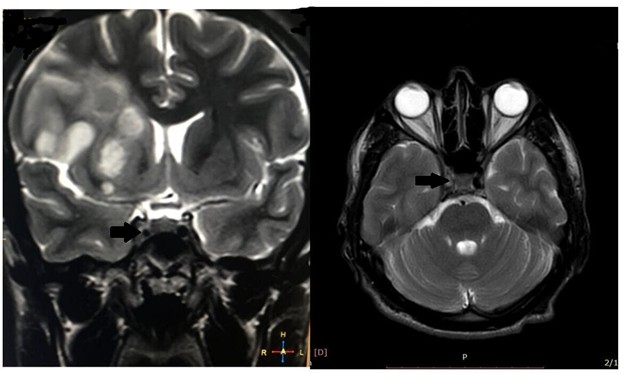

A non-contrast CT scan initially provided inconclusive results, prompting diffusion-weighted MR brain imaging, revealing an acute middle cerebral artery stroke (Figure 1). Subsequent MRI brain with MR venography demonstrated additional findings, including asymmetrical cavernous sinus and narrowed right internal carotid artery (Figure 2). Consequently, MRA of the carotid vasculature revealed a hypoplastic right internal carotid artery and abnormal appearances of the middle cerebral and anterior cerebral arteries, presenting as a beaded appearance at the petrous (C2), lateral, and cavernous (C4) segments, with collateral filling through the circle of Willis (Figure 3).

Figure 2. Axial and sagittal T2-weighted image at the level of the cavernous sinuses demonstrates the absence of signal void within the intracavernous segment of the right internal carotid artery (ICA).